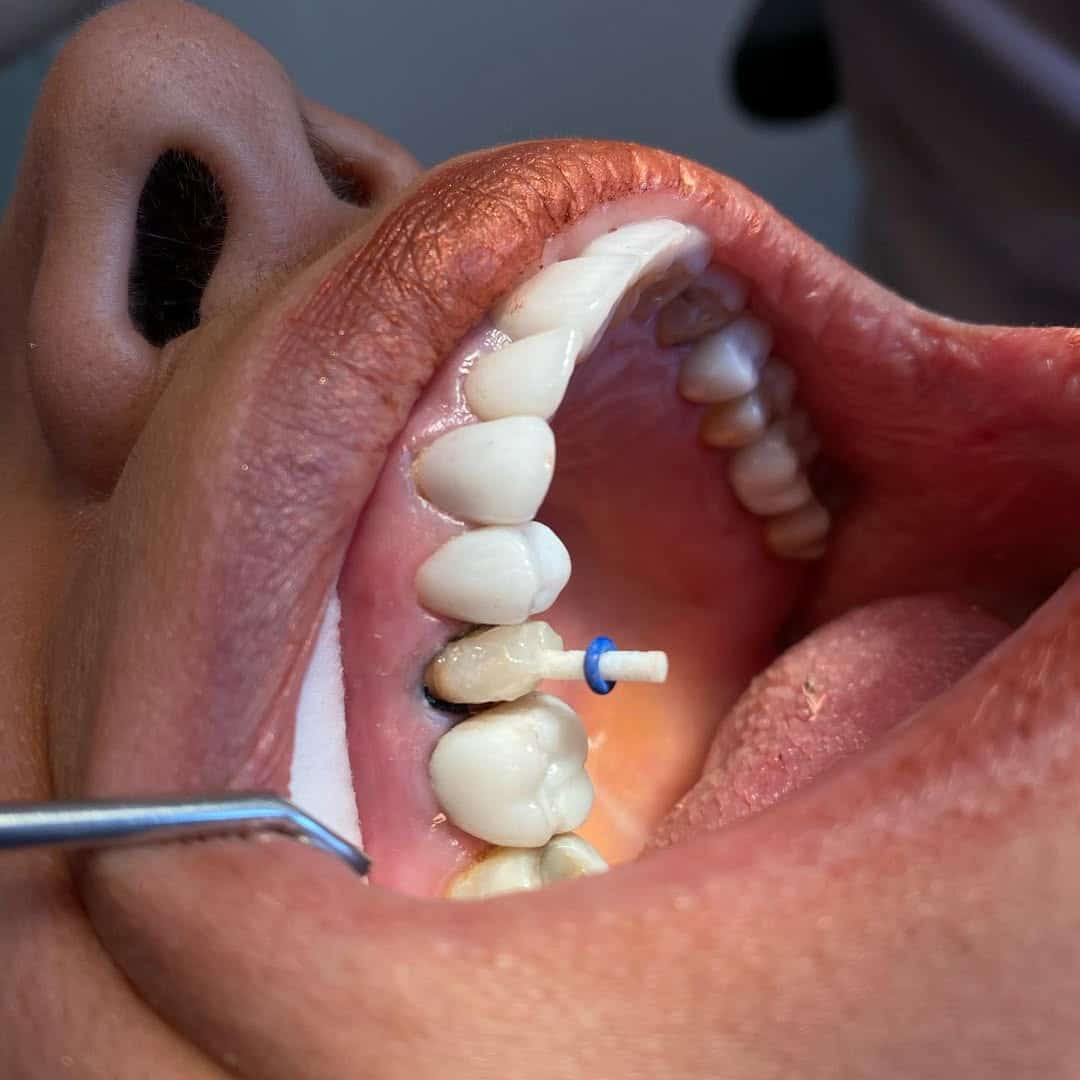

- Dolgu malzemesi ile tedavi edilemeyecek büyüklükte doku kaybı olan dişlerde

- Kanal tedavisi nedeniyle kırılgan hale gelen dişlerin korunmasında,

- İmplant üstü protez olarak da kaplama uygulanabilir.